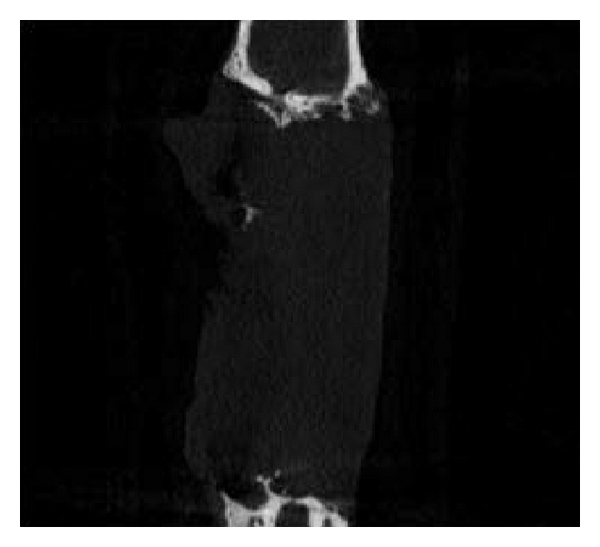

3.4. Micro-CT Examination

Micro-CT examination of 5 rabbits (2 from group A, 2 from group B, and 1 from group C) was conducted 3 months after surgery. The shapes of the rabbit bones at 3 months were shown in Figure 4. The bone defect in group A was not completely repaired, which in group B was completely repaired, while group C showed typical bone nonunion. The number of trabeculae per mm in groups A, B, and C was 0.40, 0.17, and 0.34, respectively. The bone mineral density in groups A, B, and C was 1.25434 mg/cc, 1.32521 mg/cc, and 1.3349 mg/cc, respectively, and the high bone density in group C resulted from osteosclerosis. The mass losses of PLLA and PLLA/PCL were 63.575% and 67.195%, respectively. These two scaffolds have fast initial degradation rate and then slowed down and cannot completely degrade 3 months after implantation.

(a)

(b)

(c)